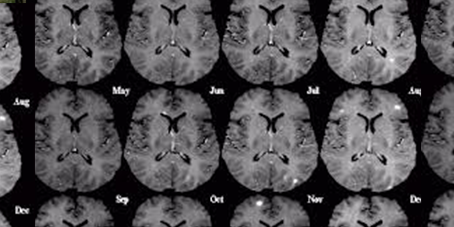

Investigadores del Centro Médico de la Universidad de Columbia examinaron cerebros, jóvenes y viejos, donados por personas que murieron sin mostrar síntomas de enfermedades neurológicas. Descubrieron que cierto gen en una parte específica del hipocampo, el centro de memoria del cerebro, deja de funcionar adecuadamente en la gente mayor. Produce menos cantidad de una proteína crucial.

Desde hace tiempo se sospecha que esa sección del cerebro, llamada el giro dentado, es especialmente vulnerable al envejecimiento. Es importante destacar que se encuentra en una sección distinta del área donde comienza a gestarse el Alzheimer.